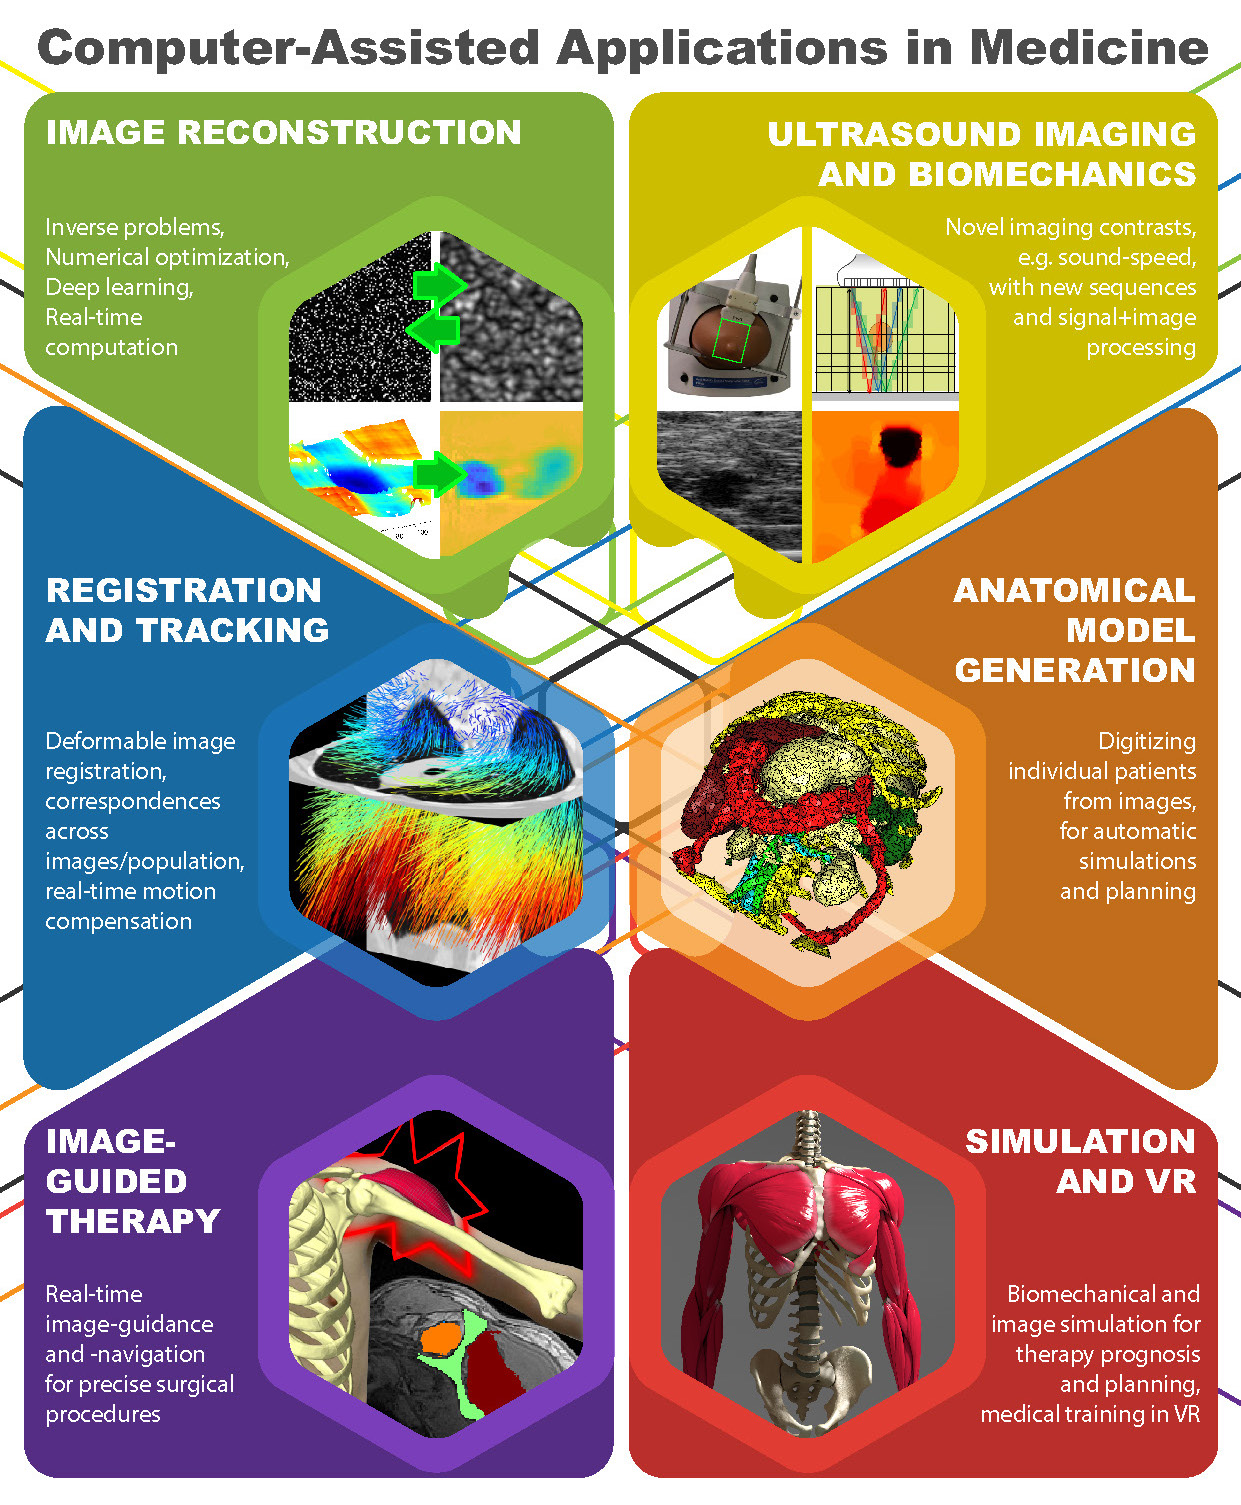

Group CAiM

Visual summary of research interests